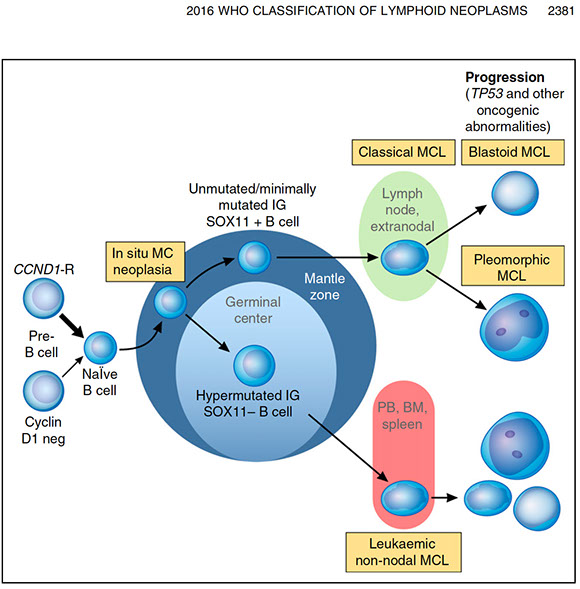

Thioflavin S (fluorescent scope needed)

IHC for Ig light chains, P component (found in most forms of amyloid), Amyloid A

Has become more and more routine to analyze amyloid with mass spec

- becoming the gold standard for amyloid typing

- IHC classification has well-known errors

- Serious consequences!!!

__________________________________________

Tx: bone marrow transplant